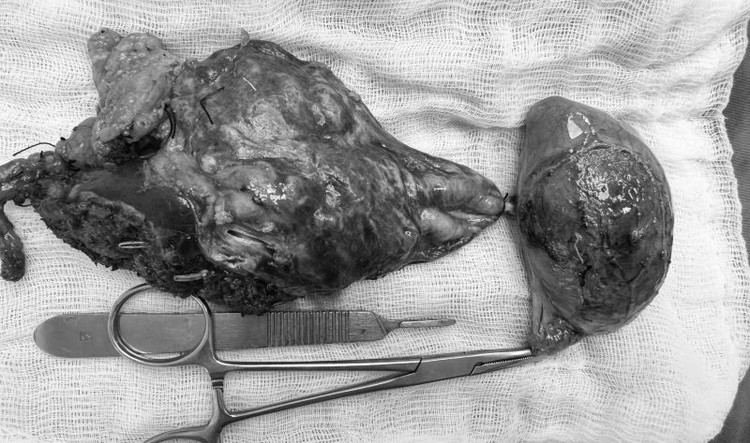

Tại đây, qua thăm khám kỹ lưỡng và thực hiện các cận lâm sàng chuyên sâu như chụp CT-scan bụng, kết quả cho thấy bệnh nhân có nhiều sỏi đường mật trong gan trái và sỏi túi mật, cùng với đó là gan trái bị xơ teo nhỏ.

Dựa trên các kết quả chẩn đoán hình ảnh, bác sĩ nhận định sỏi đã hình thành lâu trong ống mật chủ dẫn đến tắc mật, đồng thời ống gan trái bị chít hẹp khiến cho toàn bộ thùy gan trái của bệnh nhân đã bị xơ teo và tạo các túi sỏi.

Với triệu chứng đau bụng tái diễn nhiều lần, gây ảnh hưởng không nhỏ đến sinh hoạt hàng ngày nên chị H.T.K.H., (47 tuổi, ngụ Sóc Trăng) đã tìm đến Bệnh viện Đa khoa Xuyên Á Vĩnh Long để thăm khám, phát hiện bị sỏi lấp đầy ống mật chủ và gan trái, khiến cho chị bị xơ teo gan trái.

Gan trái xơ teo vì sỏi - Ảnh BVCC